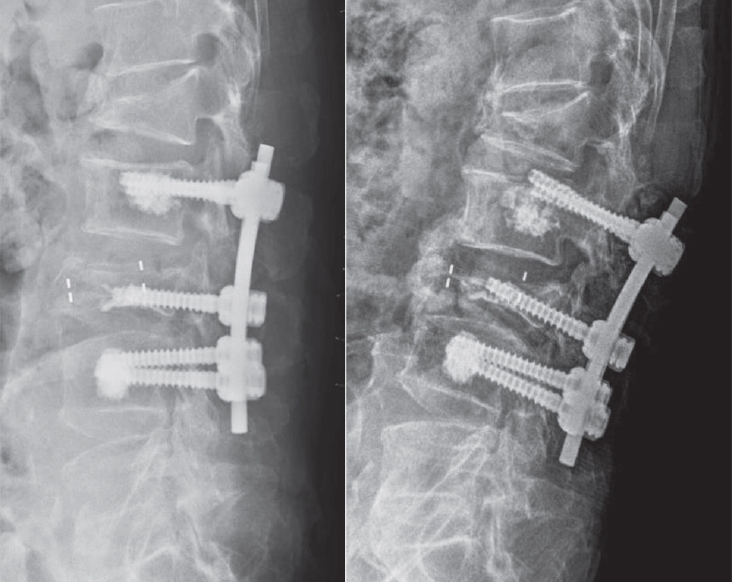

Postoperative imaging was essential for evaluating surgical outcomes. Standard radiographs and computed tomography (CT) scans were used to assess screw position and integrity. Mechanical failures—including pull-out and screw loosening—were identified by the appearance of a halo around the screw, indicating loss of fixation.10) Fig. 1 shows a typical pull-out, where the screw disengages from the vertebral body, whereas Fig. 2 demonstrates screw loosening, identified by the halo sign on CT imaging.

Fig. 1.

Postoperative radiograph demonstrating screw pull-out from the vertebral body.

Fig. 1. Postoperative radiograph demonstrating screw pull-out from the vertebral body.